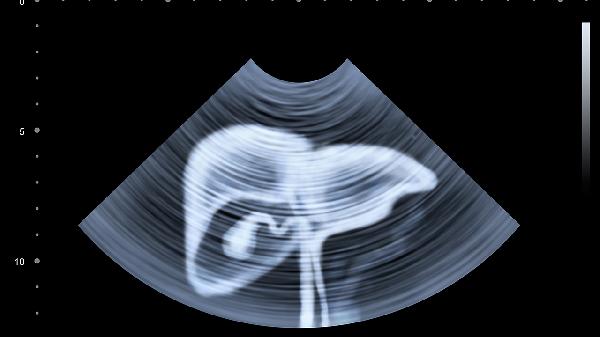

肝癌晚期不会传染。肝癌是由肝细胞异常增殖引起的恶性肿瘤,不具有传染性,但需要积极治疗以缓解症状和延长生存期。肝癌的病因包括遗传、环境因素、生理因素、外伤和其他病理因素。

1.遗传因素:部分肝癌患者存在家族遗传倾向,如遗传性血色病或家族性肝病。这些疾病可能增加肝癌的风险。建议有家族史的人群定期进行肝脏检查,如肝功能检测、B超或CT扫描,以便早期发现异常。

3.生理因素:慢性肝病如肝硬化、脂肪肝可能发展为肝癌。长期酗酒、肥胖、糖尿病等也会增加患病风险。建议控制体重、戒酒、合理饮食,并定期监测肝功能。

5.病理因素:肝炎、肝硬化等慢性肝病可能逐渐发展为肝癌。早期治疗慢性肝病是预防肝癌的关键。治疗方法包括抗病毒治疗、保肝药物和定期随访。